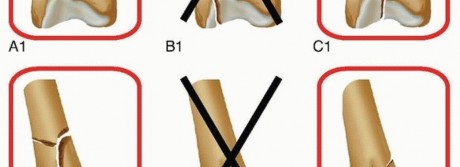

Table 1 Relative Indications for Retrograde Intramedullary Nailing of the Femur Indication Rationale All femoral shaft fractures Shown in multiple studies to have equivalent union rates and outcomes to antegrade intramedullary nailing Pregnancy Ability to decrease the amount of radiation exposure to the fetus Bilateral femur fractures Decreased overall operative time because the lower extremities can be prepared and draped together, eliminating the need to reposition for the second procedure Floating knee injuries Single surgical approach Polytrauma patient Supine positioning without bump allows for multiple surgical team approach to patient. Unstable spine injuries Supine positioning without bump affords ability to maintain spine precautions throughout the procedure. Acetabular or pelvic fractures Avoids surgical incision about the hip that may limit future surgical approaches Ipsilateral hip and femoral shaft fractures Allows each fracture to be treated with the optimal implant Ipsilateral femoral shaft fracture below a total hip replacement stem Short supracondylar retrograde nails can be used to treat the fracture with a minimally invasive technique. Morbid obesity Easier and more limited surgical approach Soft tissue wounds about the hip Avoids surgical approach of compromised soft tissues Retrograde femoral nailing is not considered to be the standard of care for treatment of more proximal subtrochanteric fractures, but in certain patient circumstances, it may be the treatment of choice ( Table 1). Subtrochanteric fractures with the lesser trochanter and piriformis fossa intact, Russell-Taylor IA fractures ( FIG 4),25 may be amenable to retrograde femoral nailing if other patient factors favor a retrograde approach. Ideally, some proximal medial cortex remains intact to act as a buttress against the nail. It is important to know how far the proximal interlocking screw holes are from the tip of the nail in the retrograde nail system available in your hospital. We recommend being able to obtain two bicortical interlocking screws above the most proximal fracture line for very proximal fractures. If possible, they should be through holes, not slots, in the nail to provide more stability. If the subtrochanteric fracture has proximal extension, including either the lesser trochanter or piriformis fossa, or both, then proximal interlocking screw fixation of the retrograde nail would be compromised and alternative fracture fixation methods should be considered. Retrograde femoral nailing may be considered in certain supracondylar distal femoral fractures. We find that Muller's AO classification system of distal femoral fractures 16 best elucidates which of these fractures can be addressed with retrograde femoral nailing ( FIG 5). Consideration for retrograde femoral nailing can be given for all extra-articular (A subgroup) fractures. It is important to know the distance between the distal interlocking screw holes and the tip of the nail in the retrograde nail system available in your hospital. We recommend being able to obtain at least two bicortical interlocking screws below the most distal fracture line for distal fractures. Nails with oblique distal interlocking options can be advantageous because of increased stability and potentially less screw head prominence.  ---

### FIG 5 • Muller's AO classification system of distal femoral fractures,16 with fracture patterns amenable to retrograde femoral nailing highlighted.

### FIG 5 • Muller's AO classification system of distal femoral fractures,16 with fracture patterns amenable to retrograde femoral nailing highlighted.  ---